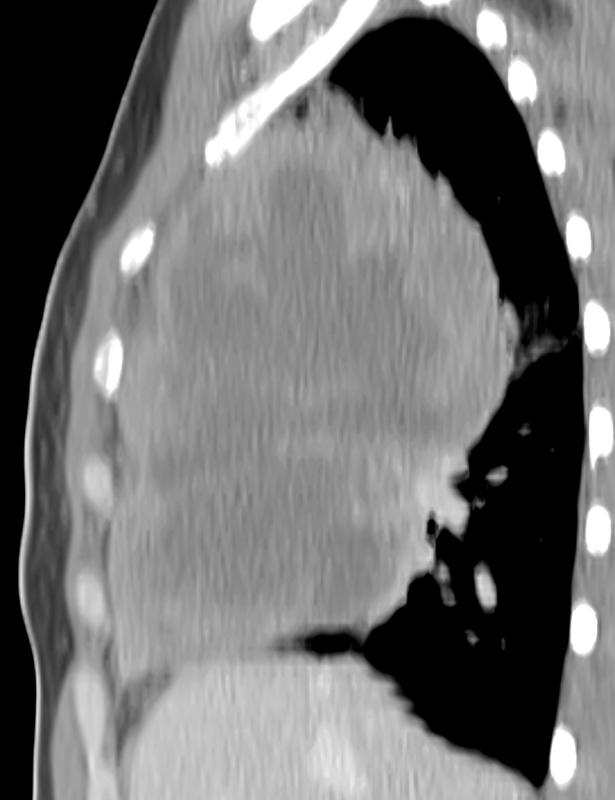

Mediastinum

Lymphoma

Lymphoma CT Sag